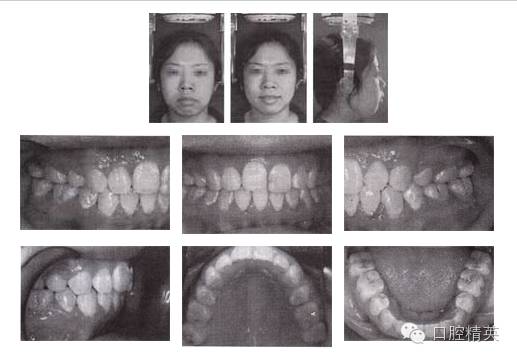

圖3-2 矯治后面像及口內(nèi)像(結(jié)束矯治 2005-04-06)

1.前牙開頜,伴有擁擠和輕度前突,上下前牙唇傾,拔除4顆前磨牙,可以解除擁擠,在內(nèi)收前牙的同時,除了可以改善面型突度,通過“鐘擺效應(yīng)”可以加深覆頜。

2.下頜選擇拔除第二前磨牙,有利于調(diào)整磨牙關(guān)系由偏遠中至標(biāo)準(zhǔn)中性。

3.對于開頜患者,不良舌習(xí)慣的破除至關(guān)重要,該患者使用了舌刺。

4.阻生第三磨牙的拔除對于開頜的矯治效果及療效的穩(wěn)定十分關(guān)鍵。

5.開頜患者通常會伴有后牙的近中傾斜,MEAW技術(shù)的應(yīng)用可以壓低并直立磨牙,有利于開頜的矯治。在MEAW使用過程中,需要將第二磨牙納入矯治序列。同時強調(diào)在前牙區(qū)使用垂直牽引。

6.矯治結(jié)束后,覆頜覆蓋正常,磨牙關(guān)系達到中性,后牙直立。

7.開頜畸形矯治結(jié)束后,用固定矯治器保持一年,再換用其他保持器。在保持器上附有舌刺,破除吐舌不良習(xí)慣,并教會患者正常吞咽動作。